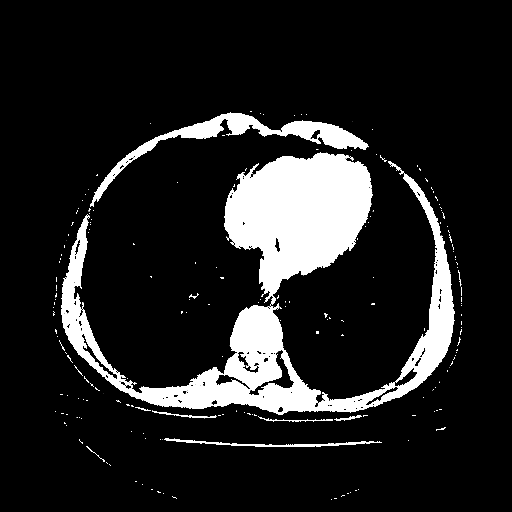

Image Grid

4Γ—3 grid: Rows show different image types (Original NATIVE, Reconstructed NATIVE, Original VENOUS, Generated VENOUS), Columns show windowing techniques (No Window, Lung Window, Mediastinum Window)

Original NATIVE CT scan (input)

Full window (WL 1023.5, WW 4095 β†’ Low βˆ’1024, High +3071)

Actual HU range: [-1024.0, 3071.0]